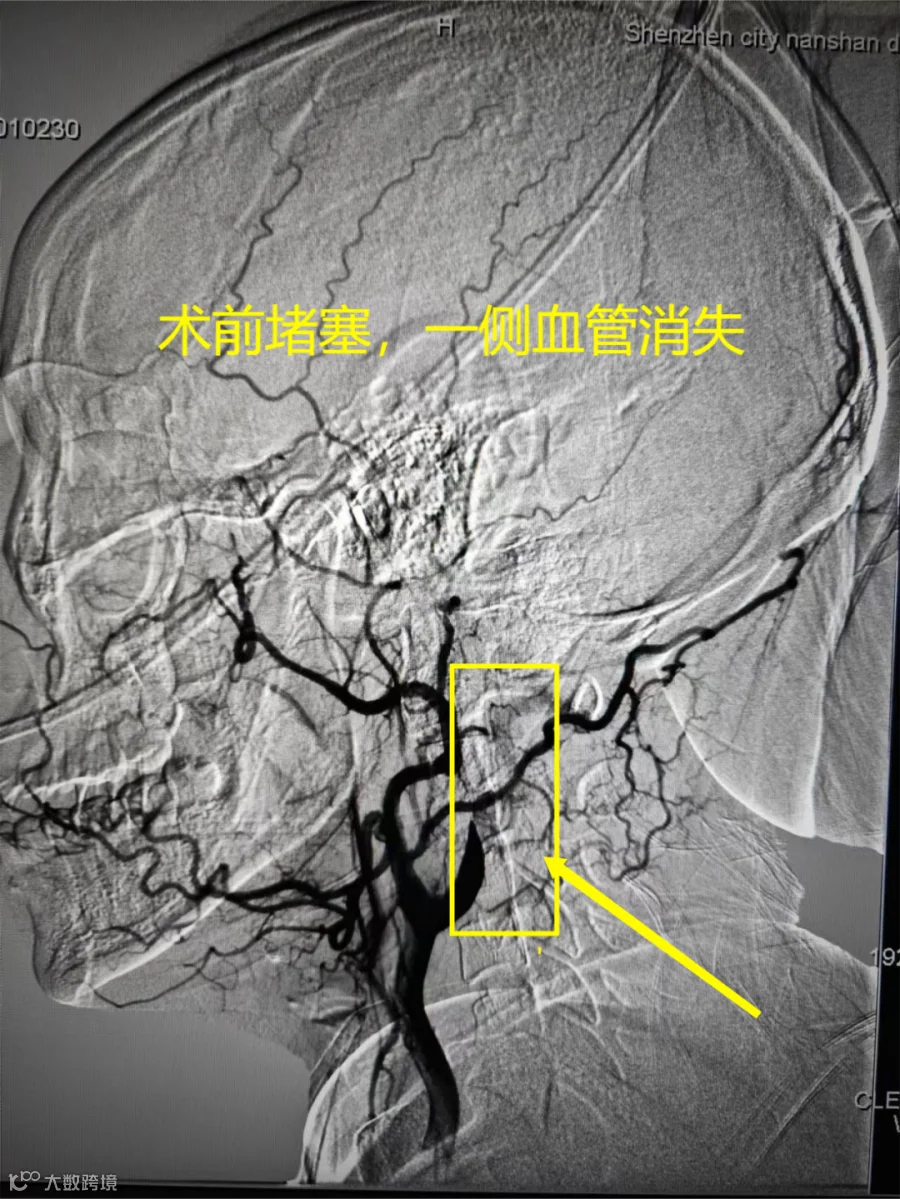

接诊的是神经内科副主任医师郭飞医生。凭借多年临床经验,他初步判断,彭女士是突发急性脑梗,中风了。

是颈动脉夹层引起的脑中风

简单来说

就是血管堵住后

脑组织梗死

无法正常工作

左脑控制的右半身就瘫痪了

医生建议立马安排手术取栓。手术结束,彭女士就恢复了“自由身”,右半边身子可以重新活动了。